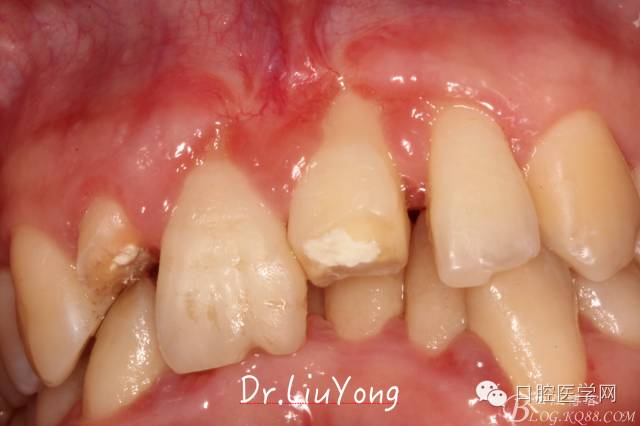

骨塊固定兩周后復(fù)查,如上圖:

在松動牙固定的同時,嘗試保留B1唇側(cè)折裂牙槽骨塊,拆除縫線后,局部沖洗,牙周塞治劑覆蓋并固定游離骨塊。囑患者加強口腔衛(wèi)生,氯己定漱口液含漱,兩周后復(fù)查。兩周后拆除塞治劑,骨塊仍為游離活動狀態(tài),去除游離骨塊,局部沖洗上藥。